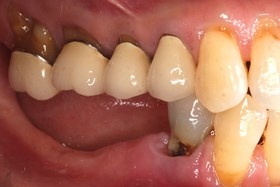

術前缺牙無法咀嚼